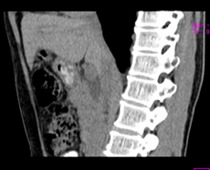

患者,男,57,常年不吃午饭,近一个月来腹部隐痛,无明显黄疸,明天进行增强扫描,图象另上传,麻烦各位帮忙一起看看讨论讨论

肝外胆管扩张,胰头增大,肠系膜上静脉似有包埋征象。

考虑:胰头占位性病变,建议增强进一步检查。

肝内外胆管扩张,胆管未端阻塞,建议mri检查

考虑肝总管或胆总管占位性病变,建议mrcp或ercp.

胰头增大,胆总管增宽,考虑胰头癌可能性大,明天看增强片有助诊断.